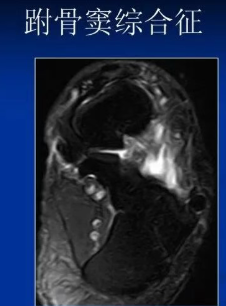

(八)跗骨窦综合征MRI检查

MRI检查适用于创伤后不明原因的持续性疼痛患者,有助于早期发现跗骨窦部位病理改变。正常跗骨窦在冠状位和矢状位MRlT1加权图像上显示高信号强度的脂肪和低信号强度的韧带组织,若跗骨窦脂肪为其他组织代替,T1、T2加权图像则均为广泛低信号强度改变,且可显示颈韧带和骨间韧带撕裂 。

跗骨窦综合征MRI诊断

异常表现:跗骨窦内软组织结构界限不清,水肿或纤维化,异常液体积聚,邻近的外侧韧带异常。病理基础为慢性滑膜炎,炎症,纤维化,滑膜囊肿。

跗骨窦综合征MRI表现

跗骨窦韧带撕裂,窦内结构模糊跗骨窦韧带纤维化(在T1WI和T2WI图像上呈低信号)

滑膜炎、液体和韧带扭伤(T1WI低信号;T2WI高信号)

在距下关节后面前、后微隐窝处的液性信号(T1WI低信号;T2WI高信号)